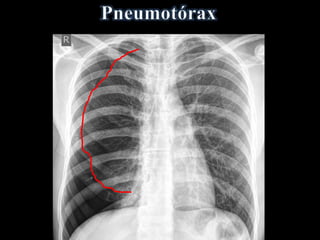

• Ar livre na cavidade pleural

• Faixa de ar (hiperlúcida) entre a pleura

visceral e:

a parede torácica e/ou diafragma

• Desvio de mediastino contralateralmente

• Acentuado na Expiração Forçada